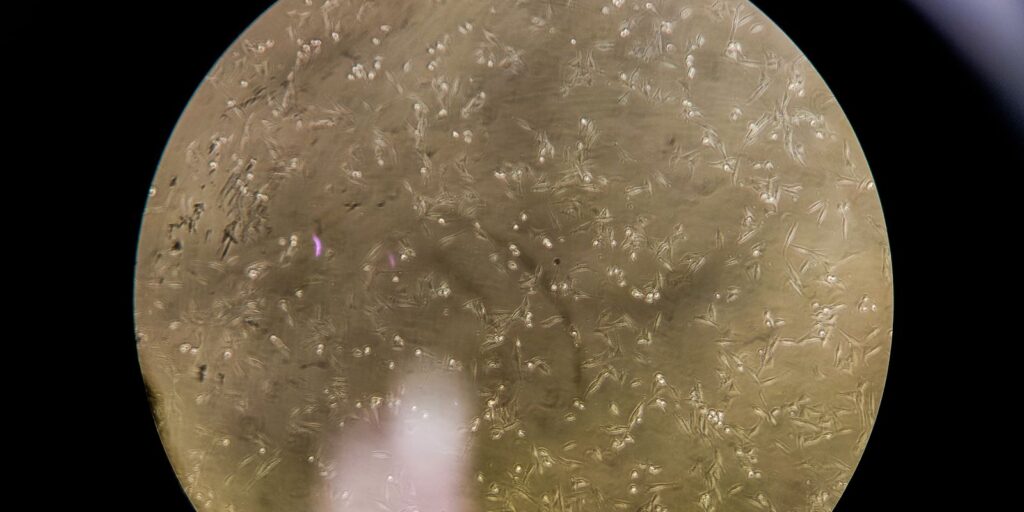

Zika pode causar resistência à insulina no cérebro, aponta estudo

Cientistas descobriram que o vírus da zika pode causar resistência à insulina no cérebro. A conclusão é de um estudo conjunto de instituições de ensino do Rio de Janeiro em parceria com pesquisadores do Instituto do Cérebro, da Pontifícia Universidade Católica do Rio Grande do Sul e da Universidade de Lund, na Suécia. Há dez […]